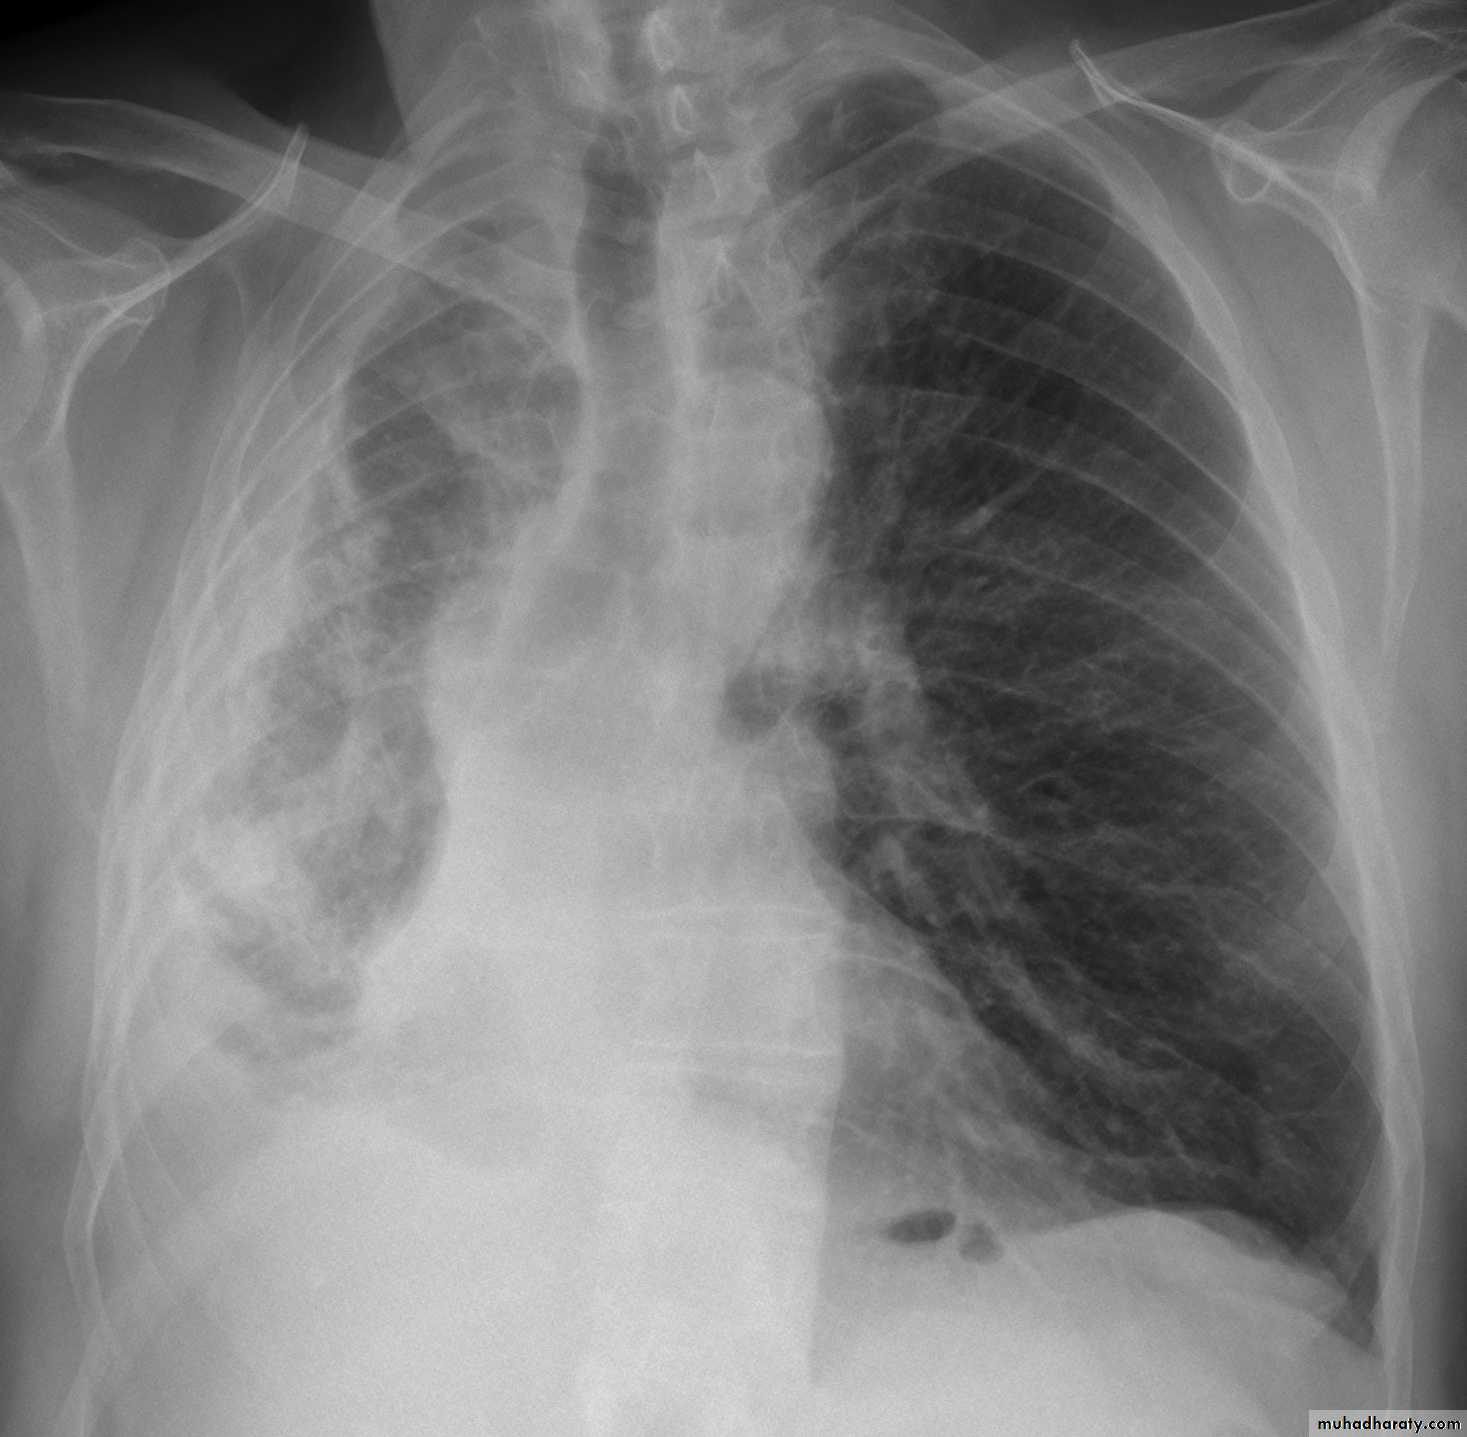

CXR:

Tension Pnenmothorax